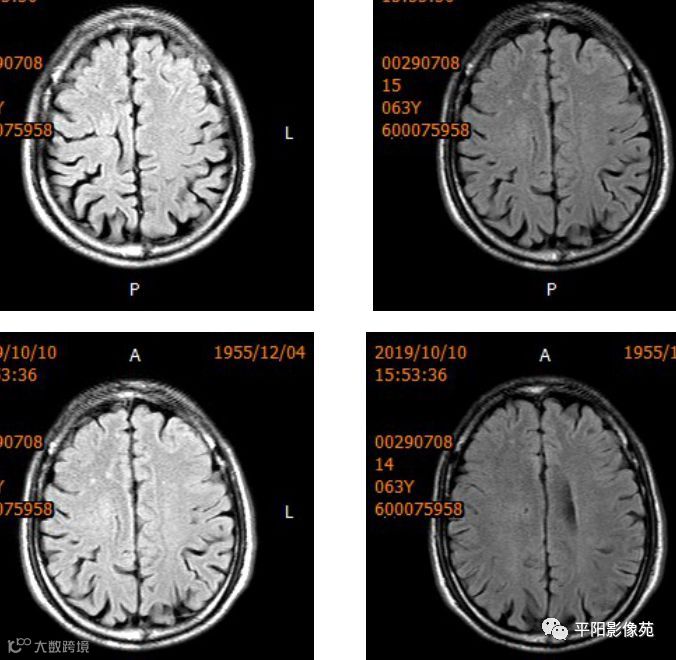

右侧额叶中央前回局部脑裂增宽,并向内延伸,周围衬以等灰质信号,呈稍长T1稍长T2信号,病灶自软脑膜向内延伸,与室管膜相连。